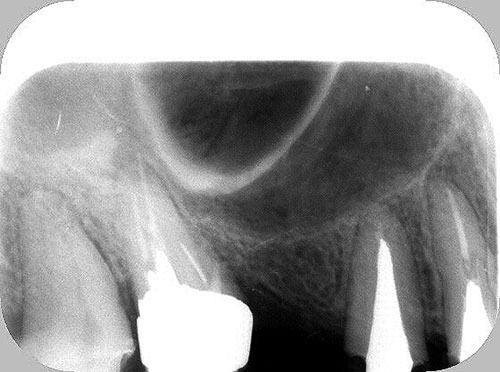

Mientras dichos movimientos ortopédicos se producen (período que supondrá otros seis meses), estudiamos los actos quirúrgicos a realizar en los cuatro implantes que pondremos. De acuerdo al estudio Desatascan realizado observamos tres situaciones diferentes: 1º-El Primer Molar Inferior Izquierdo, lo instalamos mediante Cirugía Minimamente Invasiva , con la aplicación de una Férula Quirúrgica Obtenida de los datos del scanner tratados con un programa de CMI (Cirugía Minimamente Invasiva), previa prueba en un modelo estereolitográfico, ya que la altura ósea era apenas de 9 mm. 2º- El Primer Molar Superior Derecho, se implantará mediante una ligera Elevación Atraumática (Trans alveolar) de Seno una vez logrado el espacio mesio distal necesario. 3º- El Incisivo Central Superior Derecho ausente, cuenta con un sustrato óseo prácticamente inexistente. El espesor de la tabla era de menos de 2 mm. Los caminos posibles a seguir para contar con una Rehabilitación de piezas independientes son dos: Optamos por esta segunda opción por ser menos cruenta y no necesitar de una zona dadora. Técnica esta que pondremos en práctica en dos etapas diferidas: 1º-Incisión horizontal palatinizada, incisiones peri rodetes gingivales e incisiones de descarga. Dilatación que comenzamos con dos incisiones de descarga sobre la cortical vestibular realizadas con disco. y el comienzo de la dilatación propiamente dicha mediante una hoja de bisturí, para luego seguir con un periostótomo . Recién después de alcanzada una cierta separación de la cortical vestibular de la palatina, empezamos con los dilatadores roscados. En este punto podríamos haber utilizado sin riesgos un Implante de 3,8 mm de diámetro, pero a fin de mejorar la estética del pilar emergente decidimos rellenar con material osteoconductor y osteoinductor (BiOss) y cubrir mediante membrana reabsorvible ( Bio Guide). 2º-Implantación seis meses después. Mientras se van cumpliendo los tiempos antes mencionados, y comprobamos reiteradamente la funcionalidad de la oclusión con los provisorios, tomamos impresiones definitivas y construimos primero el maxilar inferior, para definir en primer término la porción inferior de la Guía Anterior., y a nivel posterior Curvas y Microplanos. Para luego realizar los cuadrantes premolar- molar del superior: La espera de la regeneración ósea y sus tiempos pertinentes, más la espera de los tiempos de la implantación, nos obligaron a modificar las etapas del protocolo D.AT.O de manera de mantener la –D- mediante el sector superior de la GA. en provisorios, mientras fuimos resolviendo en forma definitiva los demás sectores. Ya pasados los meses necesarios para recrear un hueso adecuado en el área del Incisivo Superior Derecho, procedemos a resolver la implantación de dicha zona, observando que todo el esfuerzo dedicado al mismo había sido inútil, ya que la formación de hueso se produjo minimamente. Cuatro meses después tomamos impresiones del sector Antero Superior de la Guía Anterior, incluyendo el arrastre de un transfer . Seguimos modelando la encía con un nuevo juego de provisorios. Y se construye entonces el sector superior de la Guía Anterior. Se efectúa un control radiográfico a los 6 meses. Se ha intentado mostrar en esta Rehabilitación, que a pesar de las distintas circunstancias de cada paciente, siempre debemos tener en cuenta la necesidad de ejercer la DESOCLUSIÓN del caso como prioridad número uno, para luego perseguir la ALINEACIÓN TRIDIMENSIONAL de las arcadas y obtener así una OCLUSIÓN equilibrada. D.AT.O. ES EL PROTOCOLO QUE DEBEMOS SEGUIR EN TODA REHABILITACIÓN. BIBLIOGRAFÍA 1)William Mc Horris,B.S.,D.D.S. Oclusión. Con especial énfasis sobre :El rol funcional y parafuncional de los dientes anteriores. 2)Von Spee , Craff(Anatomista alemán, describió la curva de compensación de la articulación de molares y premolares).CURVA DE SPEE 1.89 3)Stuart,D.”Some aspects of the inervation teeth.”Procedings of Royal Society of Medicine.20:1675,19274)Muhleman,H. y Savdir,S”Tooth movility-its causes and significance”Journal of Periodontology ,36:153,Marzo ,Abril,1965. 4)Muhleman,H. Y Savdir,S”Toothmovility its causes and significance” Journal of Periodontology,36:153,marzo,abril,1965. 5-Oclusión y Diagnóstico en Rehabilitación Oral. 6-Anatomia Odontológica. 7-A contribution to the study of the movementes of the mandible. 8-Celenza F.W, Nadeskin J.F.,Oclusión.Situación actual. 9-D´Amico 10-Dawson P.E. 11-Huffman –Regenos. 12-Hobo S.-Takayama H.A. 13-Lucia V.O 14-Mc Horris. 15-Mc Horris. 16-Stuart C. 17-Vartan Veshnilian 18-Alvarez Cantoni H. AUTOR:Ratificación del Protocolo en Rehabilitación Bucal a pesar de las incidencias propias de cada caso clínico. A propósito de un caso.

Verificamos también el escaso ancho crestal, lo que nos obliga a utilizar dilatadores roscados y un osteótomo para elevar inicialmente la membrana de Schneider.

No obstante pudimos implantar satisfactoriamente mediante un implante de 4.2 mm. de ancho y 14 mm. de largo, con una nueva R.O.G.

El implante se encontraba perfectamente según comprobaciones radiográficas y clínicas al sondeo.